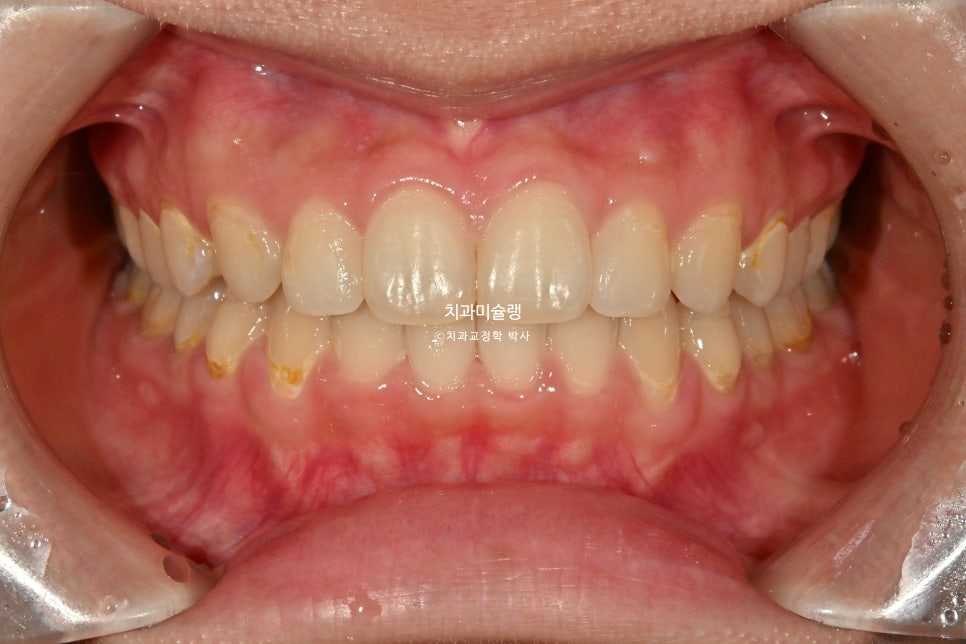

마무리 조절을 거쳐 2026년 3월, 치료를 마쳤습니다.

총 치료기간은 1년 2개월 입니다.

중심선은 정확히 맞으며 과개교합은 개선되었습니다.

브라켓 주변부 양치가 안되어 안타깝게도 충치가 좀 생겼습니다.

어금니 교합관계는 1급관계를 달성.